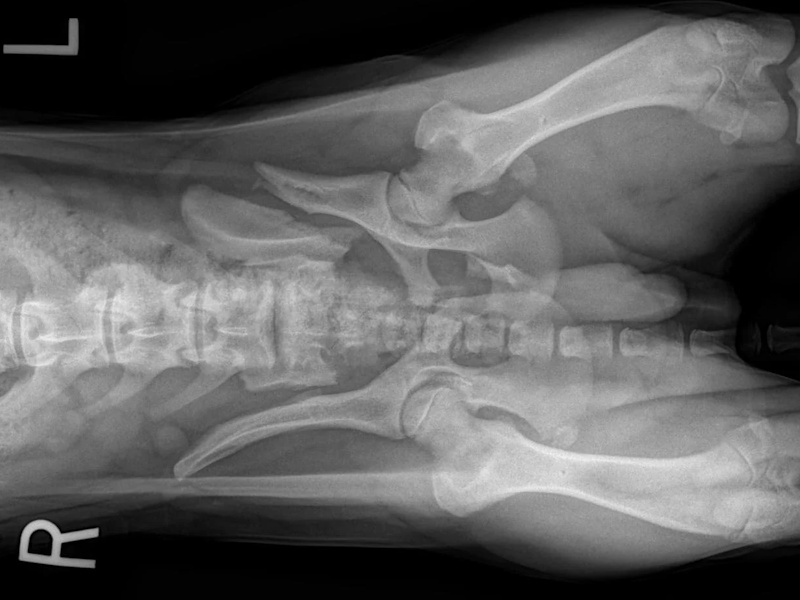

Hip Dysplasia

Hip Dysplasia in canines

Surgical Treatments of Hip Dysplasia